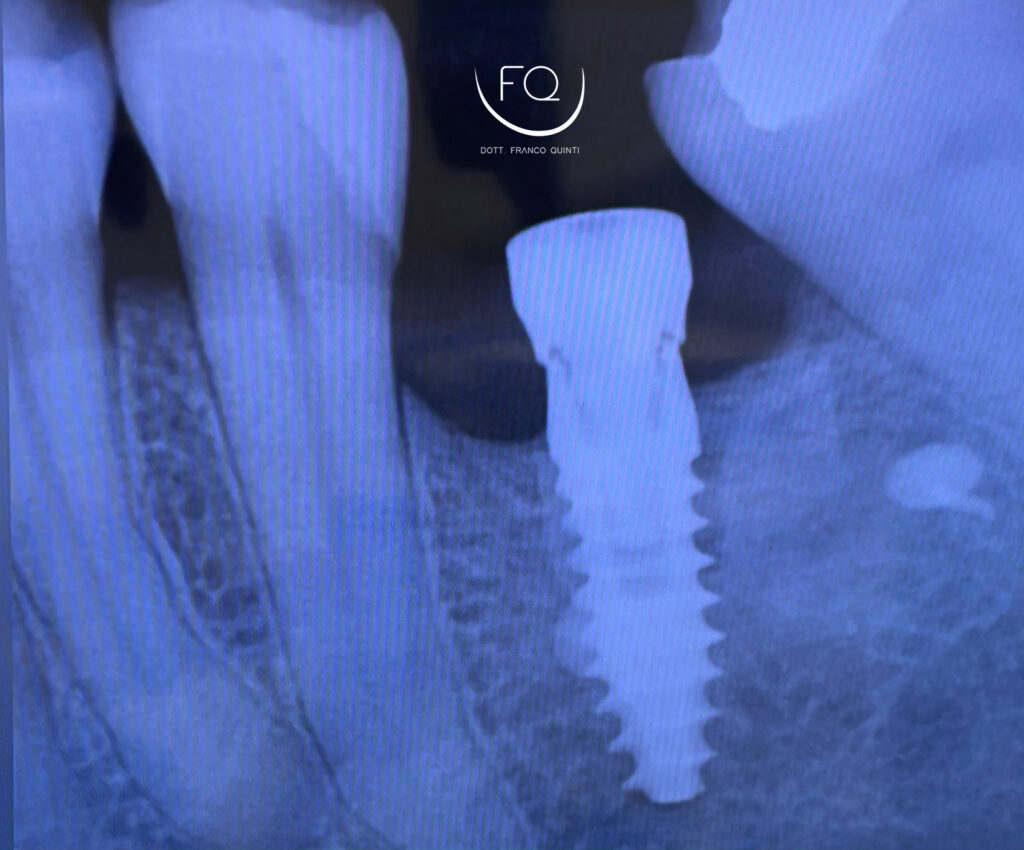

Oggi vi mostro un caso di GBR orizzontale in mandibola, trattato con un innesto a blocco fissato con vite da osteosintesi.

Dopo 4 mesi di guarigione è stato possibile procedere con l’inserimento di un impianto PRAMA di Sweden & Martina.